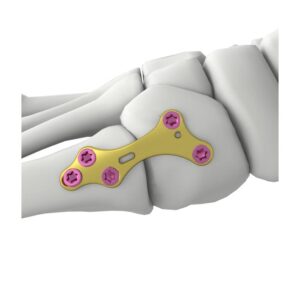

SISTEMA DE ARTROPLASTIA ANATOMICA DE LIGAMENTOS DEL PULGAR (ATLAS)

La técnica ATLAS está destinada a corregir la inestabilidad CMC del pulgar y facilitar un rápido retorno a la función mediante la colocación de fijaciones estables de anclaje basado en suturas en los sitios anatómicos de inserción del ligamento basal del pulgar.